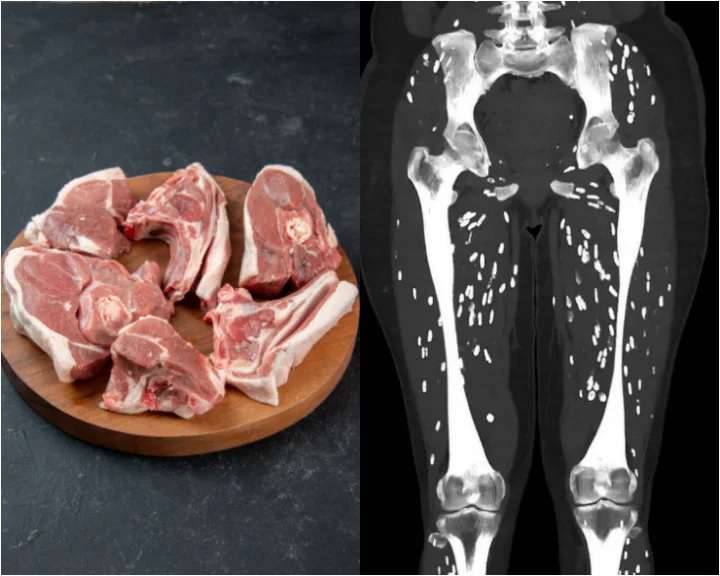

‘Craziest’ CT scan shows how eating undercooked pork affects the body

An American doctor has recently shared an image of the CT scan of a person who was suffering from a severe parasitic infection caused by eating undercooked pork.

Dr Sam Ghali, an emergency physician with the University of Florida Health Jacksonville, shared the image of the CT scan of the limbs of the patient suffering from "infamous parasitic infection" caused by the ingestion of the larval cysts of Pork Tapeworm, whose scientific name is Taenia Solium.

"Humans become infected with T Solium by ingesting cysts that can be found in undercooked pork. After several weeks (usually around 5-12) these cysts evolve within the gastrointestinal tract into mature adult tapeworms. This condition is known as Intestinal Taeniasis," Dr Ghali explained.

"These adult tapeworms then shed eggs which are in turn excreted into human feces. It's very important to note that it is only when these eggs are ingested via fecal-oral transmission, that one can develop the clinical syndrome known as Cysticercosis," he further wrote.

In certain people, the larvae can end up travelling to the brain and form cysts in the brain tissue, leading to headaches, confusion, seizures, and other serious neurologic problems, Dr Ghali further explained.

The troubling CT scan shows tiny, rice grain-like particles all around the bones in the patient's limb.

“So the moral of the story here is do your best to keep clean, always wash your hands, and never, ever eat raw or undercooked pork,” Dr Sam Ghali said.